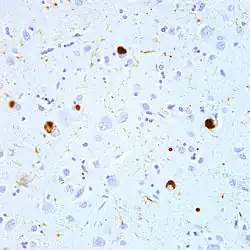

See caption.

Microscopic image of a Lewy body (adjacent to arrowhead) in a neuron of the substantia nigra; scale bar=20 microns (0.02 mm)

See cation.

This photomicrograph shows brown-immunostained alpha-synuclein in Lewy bodies (large clumps) and Lewy neurites (thread-like structures) in the neocortical tissue of a person who died with Lewy body disease.